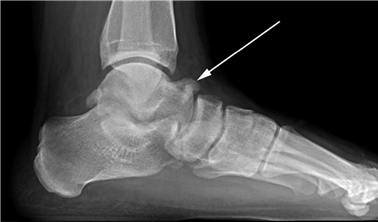

Weight-bearing anteroposterior (AP), lateral, and sesamoid axial radiographs are mandatory. On the AP view, the surgeon measures the Hallux Valgus Angle (HVA, normal < 15°), the Intermetatarsal Angle (IMA, normal < 9°), and the Distal Metatarsal Articular Angle (DMAA). The lateral view is scrutinized for Meary's angle (talo-first metatarsal angle) to identify midfoot collapse, as well as the presence of dorsal osteophytes indicative of hallux rigidus. The sesamoid axial view is critical for assessing the degree of sesamoid subluxation and the integrity of the crista.

Image

Avascular necrosis of the metatarsal head is a devastating complication primarily associated with distal osteotomies. It presents with insidious onset of pain, swelling, and eventual radiographic collapse of the articular surface. Prevention is paramount and relies on preserving the plantar-lateral soft tissue attachments during the lateral release. If symptomatic AVN occurs and progresses to joint destruction, the definitive salvage procedure is a first MTP arthrodesis, often requiring structural bone grafting to restore metatarsal length.